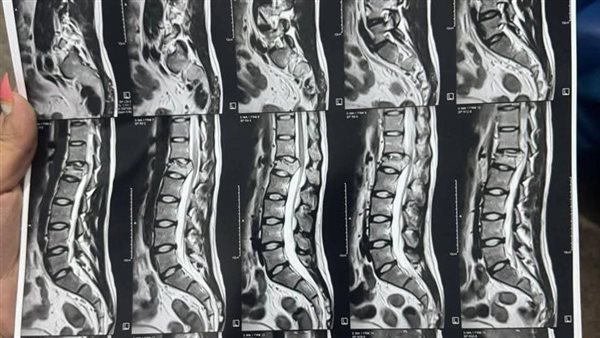

نجح فريق طبي بمستشفى قويسنا المركزي بمحافظة المنوفية، في إنقاذ حياة شاب يبلغ من العمر 25 عامًا من ذوي الاحتياجات الخاصة، بعد نقله إلى قسم الطوارئ إثر سقوطه من الطابق الثاني وإصابته بكسر في الفقرة القطنية الأولى أدى إلى ضغط على الحبل الشوكي وضعف بالطرفين السفليين.

وجرى التدخل الجراحي العاجل له، وذلك بعد إجراء الفحوصات والأشعة اللازمة، حيث تقرر تثبيت الفقرات بشرائح ومسامير مع توسيع القناة الشوكية وتسليك مخارج الأعصاب، بمشاركة الدكتور عبد العزيز المصري أخصائي التخدير وفريق من التمريض وفنيي التخدير والأشعة.